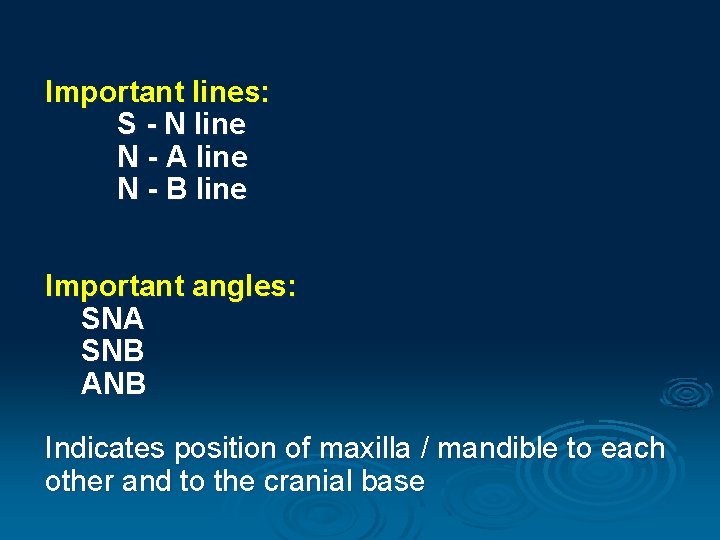

Important lines: S - N line N - A line N - B line Important angles: SNA SNB ANB Indicates position of maxilla / mandible to each other and to the cranial base